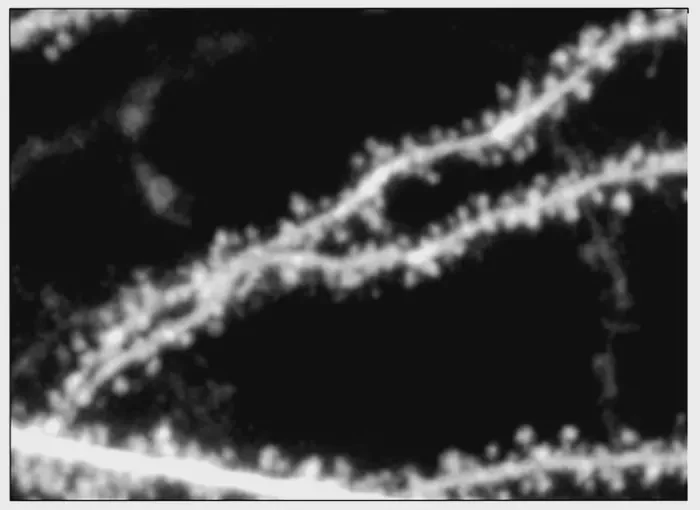

At the heart of this research is the discovery that NMDA receptors are not merely conduits for ion flow, but hold intricate signaling mechanisms that can be manipulated for therapeutic benefits. Previous studies had shown that calcium ions flowing through these receptors prompt forms of synaptic plasticity, which are essential for the brain’s adaptation to experiences. However, the 2020 study revealed a different mode of receptor signaling—one that does not involve ion flow—highlighting an essential pathway for regulating protein synthesis and thereby influencing neuronal structure, particularly the dendritic spines that play a key role in synaptic connections.

This current investigation builds on these prior discoveries, utilizing the insights on NMDA receptors to dissect their contributions to synaptic functions in a sophisticated manner. The pivotal component of this research was the molecular subunit known as GluN2B. The team identified that altering this specific receptor subunit altered the dynamics of protein synthesis and synaptic structure. By examining the genetic contributions of GluN2A and GluN2B, they determined that while both are essential for triggering synaptic plasticity, it is the GluN2B subunit that uniquely governs the physical structure of dendritic spines. This is a significant revelation, as it pinpoints a potential target for therapeutics aimed at reversing the symptoms of fragile X syndrome.

Researchers employed advanced genetic manipulation techniques to selectively inactivate the two different subunits of NMDA receptors in their model organisms. Their findings were illuminating; the absence of the GluN2B subunit alone caused alterations in spine morphology, indicating its unique role in determining synaptic structure. This contrasts sharply with GluN2A, which, when knocked out, did not affect spine size. This dissection of the NMDA receptor components offered a deeper understanding of how disruptions in these proteins can lead to conditions such as fragile X syndrome.

To further investigate the signaling pathways governed by the GluN2B subunit, the researchers turned their attention to its carboxy-terminal domain (CTD). The CTD is integral to how the receptor communicates within the cell, influencing downstream effects like spine morphology. Experimental manipulation revealed that modifications to the CTD of GluN2B can completely obliterate its influence on spine structure, thereby emphasizing its role in mediating important cellular functions.